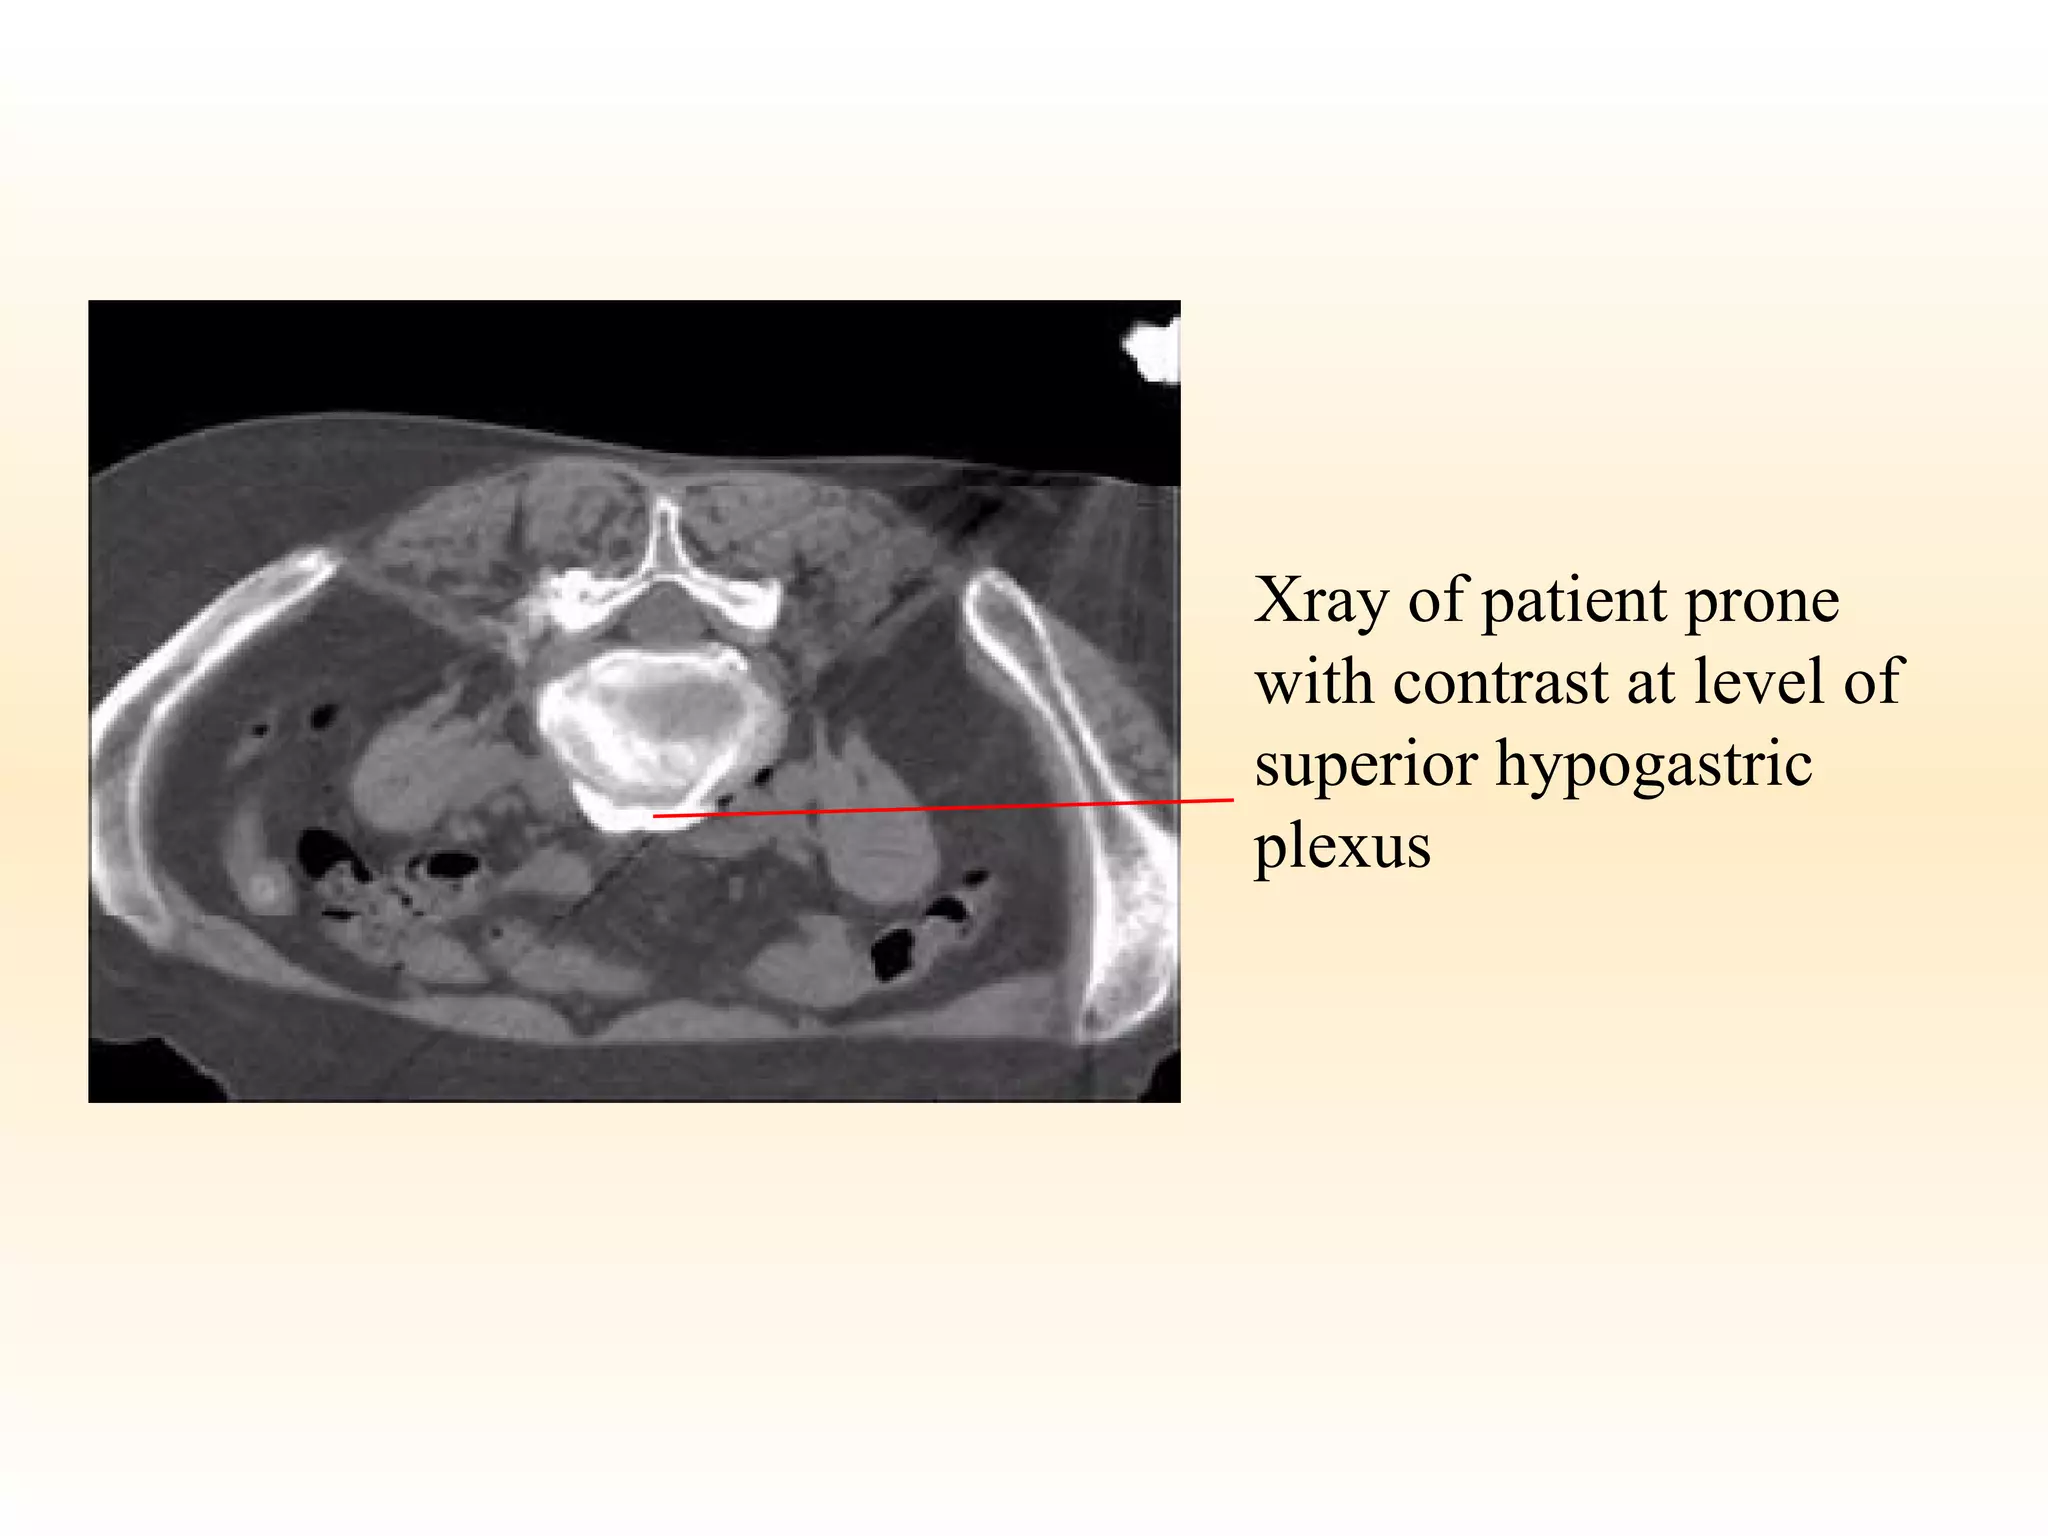

Superior Hypogastric Plexus Blockade. Relatively recent introduction.  Similar to coeliac but lower: ? ideal for pelvic invasion. Seems to have fewer side effects.

Xray of patient prone with contrast at level of superior hypogastric plexus

Superior hypogastric block L5/S1 Line of psoas Contrast in retroperitoneal space Front view Lateral view

Superior Hypogastric PlexusBlockade. Relatively recent introduction. Similar to coeliac but lower: ? ideal for pelvic invasion. Seems to have fewer side effects.

Xray of patientprone with contrast at level of superior hypogastric plexus

Superior hypogastric blockL5/S1 Line of psoas Contrast in retroperitoneal space Front view Lateral view